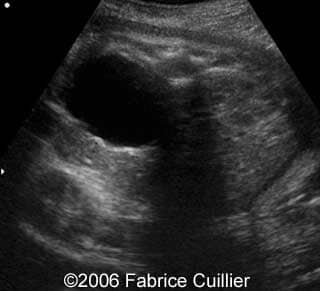

This is a 24- year-old-primigravida scanned at our unit at 21 weeks. During the first trimester, the nuchal translucency and the triple test were normal. At the end of the second trimester, the sonographer diagnosed a left polycystic kidney. The right kidney was normal with a normal corticomedular differentiation. The bladder was also normal. The patient refused additional investigations. We performed a scan at 21 weeks. The ultrasound findings were:

• an abnormal polycystic left kidney (34 X 17 mm) with an abnormal corticomedullar differentiation. This kidney was on the lumbar fossa.

At 24 and 26 weeks, the left kidney lesion had increased. At 34 and 37 weeks, the anomalies were the same. The baby was delivered vaginally (male, 3000 g). At day five, the kidney abnormalities were confirmed. Nevertheless the creatinine level was normal. One month later, a scan revealed a normal right kidney (50 mm) and a left kidney with cysts. The creatinine level was in the normal range. The child was operated (left nephrectomy). The diagnosis of multicystic kidney disease was confirmed.